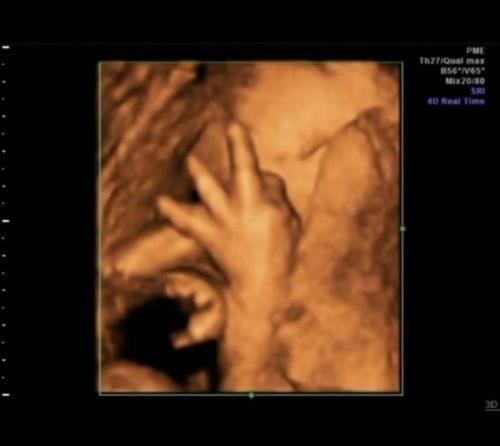

许多怀孕的母亲在进行4D拍摄时发布了自己的照片,发现婴儿的动作“奇妙”,有些会“食指”,有些在“笑”,并且婴儿在玩脐带。当然,这是正常现象。